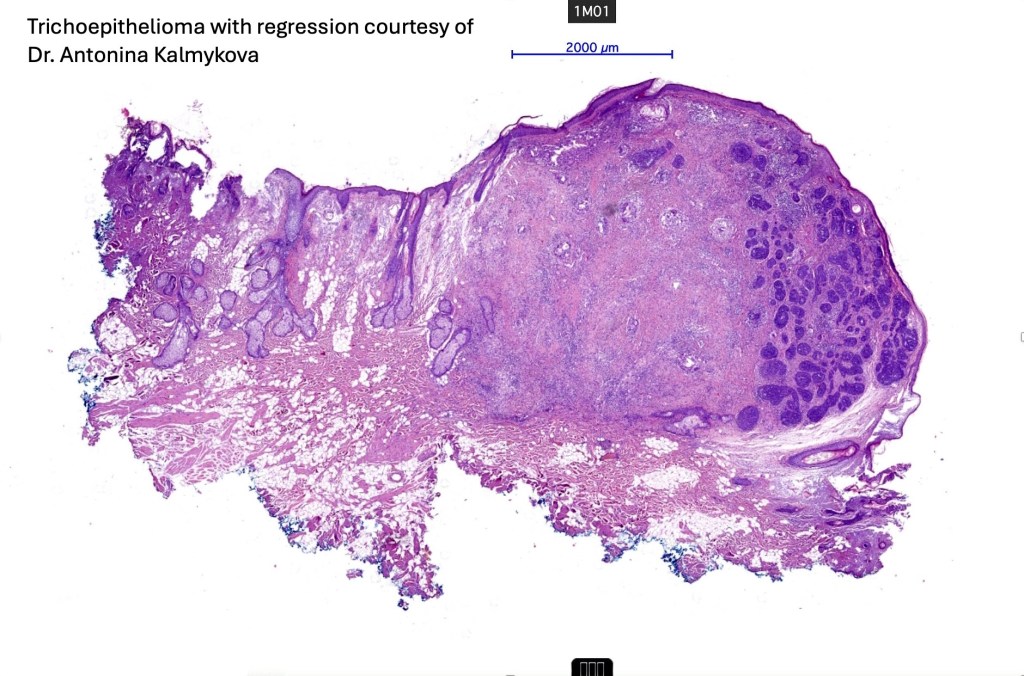

Trichoepithelioma is a hamartoma comprising a basaloid/germinative component and a prominent perifolliclular sheath proliferation. It may present as a solitary lesion or as multiple, familial lesions in multiple familial trichoepithelioma (which is probably a variant of Brook-Spiegler syndrome) & Brook-Spiegler syndrome.

Histological features

•The classical appearance consists of keratocysts & lobules of basaloid cells

Trichoepithelioma should be distinguished from trichoblastoma since the latter is very rarely syndromic. Trichoepithelioma is largely a dermal tumor whereas trichoblastoma often extends from the dermis into subcutaneous fat or deeper in very large examples. Papillary mesenchymal bodies are much better formed and generally more obvious in trichoepithelioma. Trichoepithelioma must also be distinguished from basal cell carcinoma. Retraction artifact & stromal mucin are features of basal cell carcinoma and not trichoepithelioma. Papillary mesenchymal bodies are not seen in basal cell carcinoma.